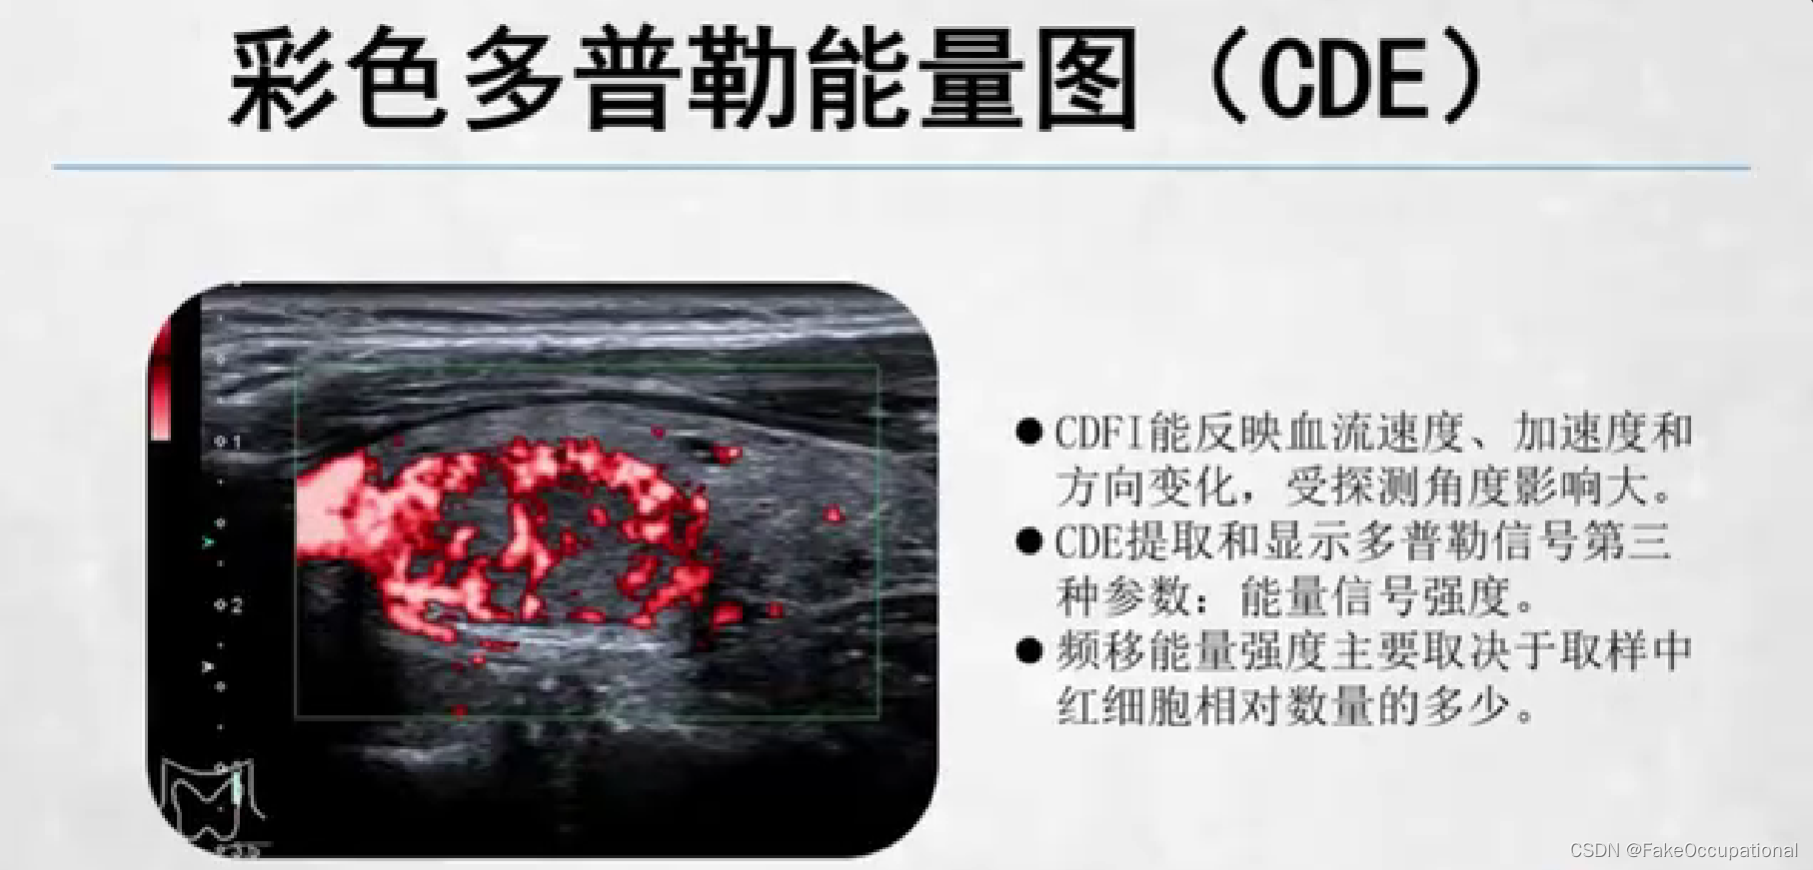

- 彩色编码实时显示血流方向、速度及血流性质:彩色多普勒血流成像(CDFI),彩色多普勒能量图(CDE)